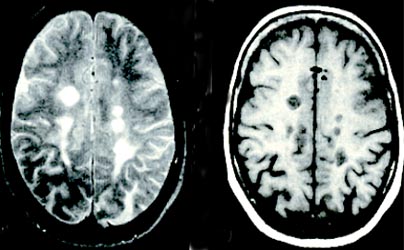

O diagnóstico definitivo de EM passa pela demonstração de disseminação temporo-espacial de lesões inflamatórias na substância branca do SNC. Para além da clínica a disseminação espacial destas lesões pode pôr-se em evidência recorrendo a técnicas neurofisiológicas (Potenciais Evocados Multimodais) e de Imagem (RNM). Embora as imagens não sejam específicas, a RNM revela lesões encefálicas em cerca de 98% de doentes com diagnóstico definitivo (Fig. 3).

| RNM: Lesões típicas de esclerose múltipla. Hiperintensas em T2 (1 e 3) e hipointensas em T1 (2 e 4) |

Fig. 3